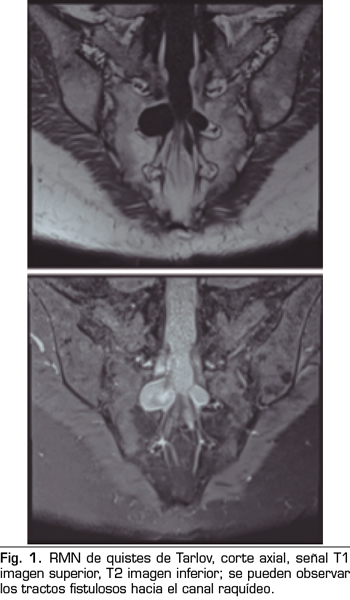

Se realiza una RMN donde no se observan alteraciones estructurales que justifiquen las dolencias que presenta. Como hallazgo casual se describen quistes de Tarlov a nivel de S2. Se solicita una valoración por el servicio de neurocirugía, quienes dudan que la clínica sea consecuencia de los quistes (Figuras 1 y 2).

No obstante, debemos tener en cuenta las variaciones anatómicas como son los quistes de Tarlov, a expensas de las capas más internas de las meninges, la piamadre y el aracnoides. Estos quistes principalmente se sitúan en la zona sacra y lumbar, y suelen diagnosticarse de manera incidental en el transcurso de una RMN. Aunque la clínica producida por los mismos no es frecuente, se deben tener en cuenta como posible diagnóstico diferencial ante posible dolor lumbar crónico.